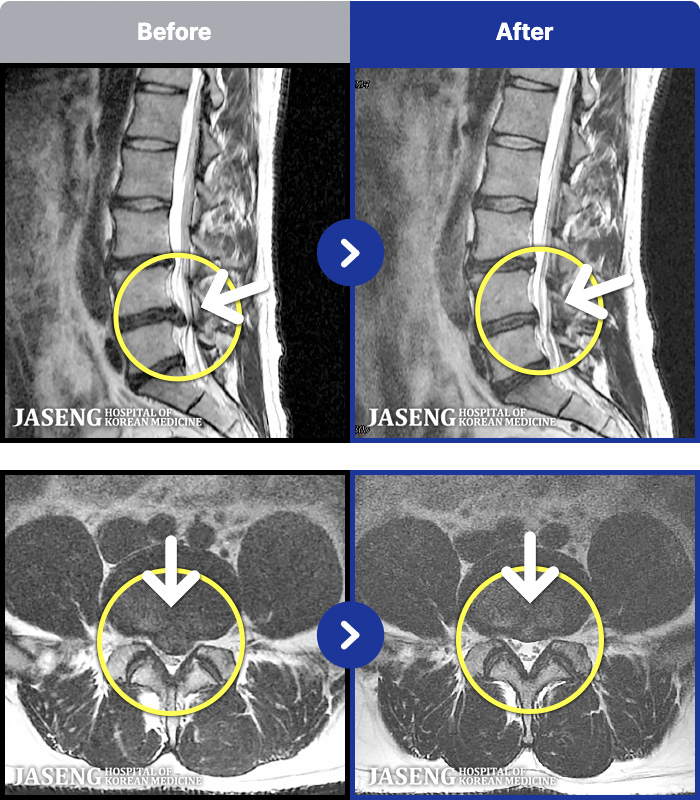

MRI ġ

MRI ũ ʸ Ȯϼ.